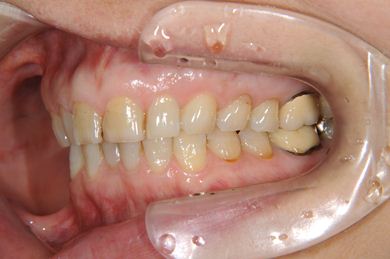

部分矯正治療+セラミック治療

| 性別/年齢 | 女性 / 54歳 | ||||||||||||||||||||||||||||||||

| 主訴 | 下の前歯のゆがみが気になり、相談。 | ||||||||||||||||||||||||||||||||

| 治療方針 | 上顎前歯の叢生を部分矯正にて審美的回復を行い、上顎前歯はラミネートベニアにて審美的回復を行う。 | ||||||||||||||||||||||||||||||||

| 治療内容 | 唇側部分矯正(ホワイト)、オールセラミックラミネートベニア8本 | ||||||||||||||||||||||||||||||||